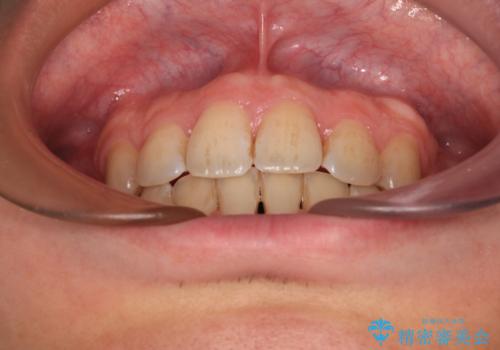

出っ歯と八重歯 目立たない裏側装置でスッキリとした口元に

上下顎で左右差の大きい抜歯矯正を裏側装置で行ったため、非常に時間がかかりましたが、正中位置も良い位置に改善され、気になっていた突出感も解消されました。